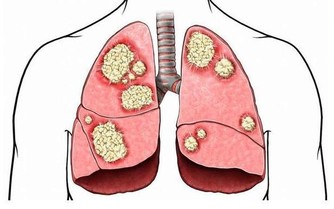

靜脈曲張是指由於血液淤滯、靜脈管壁薄弱等因素,導致的靜脈迂曲、擴張。

由於先天性血管壁膜比較薄弱或長時間維持相同姿勢很少改變,血液蓄積下肢,

在日積月累的情況下破壞靜脈瓣膜而產生靜脈壓過高,是血管突出皮膚表面的症狀。